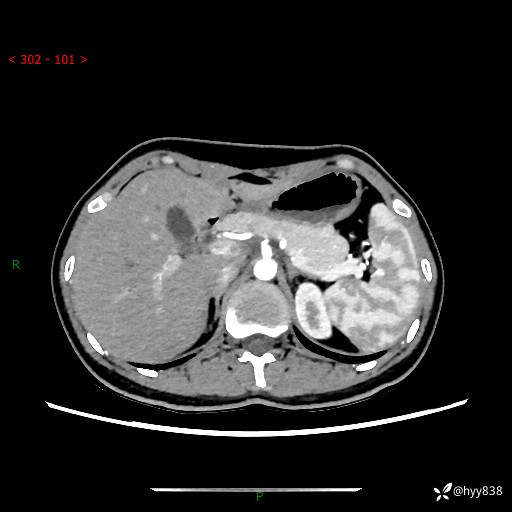

性别:女

年龄:23岁

简要病史:外院发现肝结节,来我院进一步增强确诊

上腹部CT平扫+增强

肝囊肿 (68)